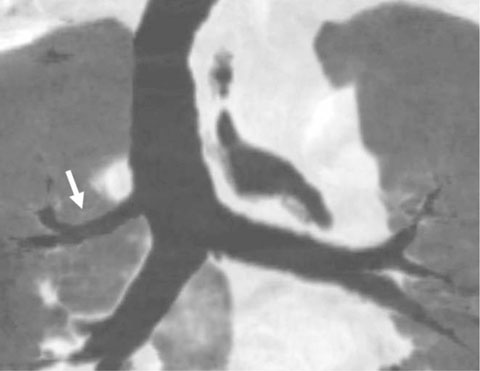

Tracheobronchial Branching Anomalies

- There are various congenital anomalies with respect to the number, length, diameter, and location of tracheobronchial branching patterns. The tracheobronchial anomalies are classified into two groups. The first one, anomalies of division, includes tracheal bronchus, cardiac bronchus, tracheal diverticulum, pulmonary isomerism, and minor variations. The second one, dysmorphic lung, includes lung agenesis-hypoplasia complex and lobar agenesis-aplasia complex.